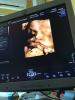

Девочки , привет )🤗 как у вас дела?) Хотела спросить кто делал 3D узи )) Сколько стоит ?) кто где делал ?) Кому где больше понравилось

Панацея, врач Поморцева, такое УЗИ сделала, была у неё 3 раза на приёме и все были с 3д УЗИ, показала всё и объяснила 😍

На первом приёме была моя мама, она ей тоже всё объяснила и показала на экране, на втором муж, там тоже всё сказала, потом фотографировала на аппарате УЗИ и когда мы закончили я на свой телефон сфотографировала, приём каждый минут 30-40 , пока всё не поймете, стоит 1600 с 16 недель)

Делать лучше в 25-27 недель , по опыту ))

@slepysevadara14, я в 33 недели делала с дочей ) неплохо получилось

Панацея - у врача Поморцевой) она мне понравилась, знаю ее со своей ЖК))) 1800₽ само узи и по 100₽ каждое фото)))) Поморцева дала нафоткать на телефон и даже засняла видео, как жует малыш))